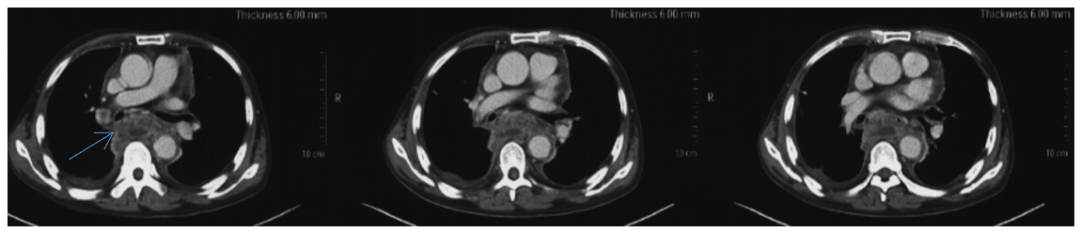

患者入院前4月(2020年11月)曾有短暂腹痛,腹盆CT(2020-11-10)示腹盆腔积液,肝门区及腹腔囊状低密度影(图3)。血淀粉酶升高,停用甲泼尼龙片,禁食、抑酶等治疗后好转。2月余(2021年1月)前患者胸闷、气短加重,就诊于外院查胸腔超声(2021-01-05)示双侧胸腔积液(左侧为著),再次加用甲泼尼龙16mgqd po×8天,2021-1-14更换为曲安西龙16mgqdpo×12天,气短症状进行性加重,胸部CT(2021-1-18)示右肺条索影,右侧少量胸腔积液,左侧大量胸腔积液(图4),予胸腔穿刺引流,为黑红色胸水,共引流3000ml,带管出院。出院后引流约900ml胸水,活动后仍有气短,1月余前(2021年1月27日)再次就诊于某结核病专科医院,停用激素,查胸部CT(2021-1-27)示右侧胸膜增厚,左侧叶间胸腔积液、纵隔囊肿(图5),继续引流胸水,胸水细胞学分类:嗜酸细胞0% 间皮细胞30% 上皮细胞0% 中性粒细胞5% 淋巴细胞65%。患者间断咳嗽加重,咳白痰,复查胸部CT(2021-2-7)示纵隔混杂密度影较2021-1-27增多(图6),予拉氧头孢1gq12h抗感染,经胸水引流后,气短好转,出院后继续口服曲安西龙16mgqd po。

图4:2021-1-18胸部CT:右肺条索影,右侧少量胸腔积液,左侧大量胸腔积液。